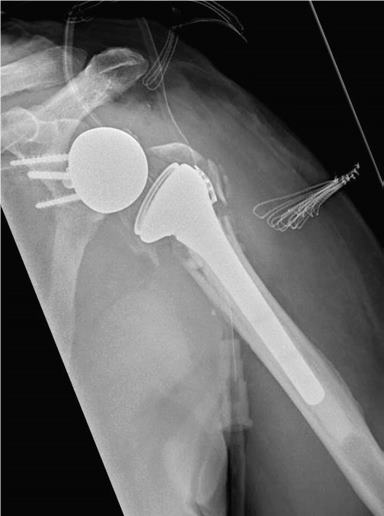

Während bei jüngeren Patienten die Rekonstruktion von Knochen und Gelenken im Vordergrund steht, führt bei älteren Patienten häufig der Gelenkersatz zur schnelleren Wiederherstellung der Beweglichkeit.

Hierfür kann die umfangreiche Erfahrung der orthopädischen Klinik in der Schulterendoprothetik angewandt werden. Dazu werden die Art der Endoprothese und die Einsatzmöglichkeit individuell geplant und umgesetzt.